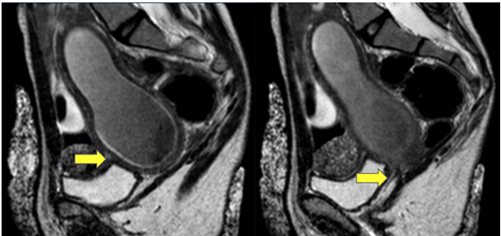

Figure 2. Magnetic Resonance Imaging (RMI)

Figure 2A: The yellow arrow indicates an enlarged uterus with hematometra. The anteverted uterus measures 100 x 32 x 59 mm, with the endometrium divided by a 90° angle indentation, creating two cavities (incomplete septate uterus).

Figure 2B: No external opening, hematometra. The vagina is not visible, showing a hyperintense fibrous image in T1 and T2, suggesting a vaginal remnant (hypoplastic vagina).